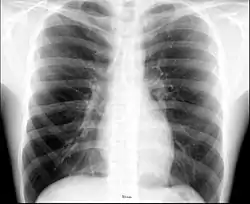

The thorax (pl.: thoraces or thoraxes)[1] or chest is a part of the anatomy of mammals and other tetrapod animals located between the neck and the abdomen.[2][3] In insects, crustaceans, and the extinct trilobites, the thorax is one of the three main divisions of the creature's body, each of which is in turn composed of multiple segments.

The human thorax includes the thoracic cavity and the thoracic wall. It contains organs including the heart, lungs, and thymus gland, as well as muscles and various other internal structures. Many diseases may affect the chest, and one of the most common symptoms is chest pain.

In humans and other hominids, the thorax is the chest region of the body between the neck and the abdomen, along with its internal organs and other contents. It is mostly protected and supported by the rib cage, spine, and shoulder girdle.